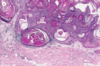

Outline the pathophysiology of bullous pemphigoid.

- Autoimmune disorder driven by IgG and C3 which attack the basement membrane

- They recruit eosinophils which release elastase which further damages anchoring proteins (anchoring lower keratinocytes to the basement membrane)

How can bullous pemphigoid be definitively diagnosed?

Immunofluorescence will show IgG and C3 along the dermo-epidermal junction